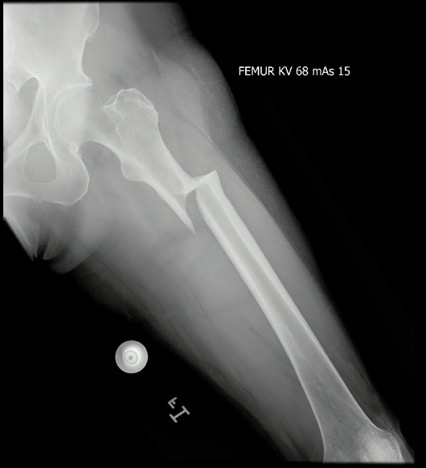

El caso corresponde a una paciente de 72 de edad, natural y procedente de la ciudad de Bogotá, con antecedente de osteoporosis en tratamiento con alendronato a frecuencia semanal durante 10 años. Consultó por presentar dolor de leve intensidad en el muslo izquierdo que empeoraba con el apoyo sobre la extremidad, sin haber presentado ningún trauma previo. En el estudio de imágenes de radiografía evidenció un engrosamiento de la cortical lateral del fémur izquierdo en la región subtrocantérica y una sospecha de una fractura unicortical atípica (figuras 1 y 2).

Radiografía en proyección AP del fémur izquierdo, donde se evidencia un engrosamiento de la cortical lateral del fémur izquierdo.

Figura 1: Radiografía en proyección AP del fémur izquierdo, donde se evidencia un engrosamiento de la cortical lateral del fémur izquierdo.

Fuente: los autores.